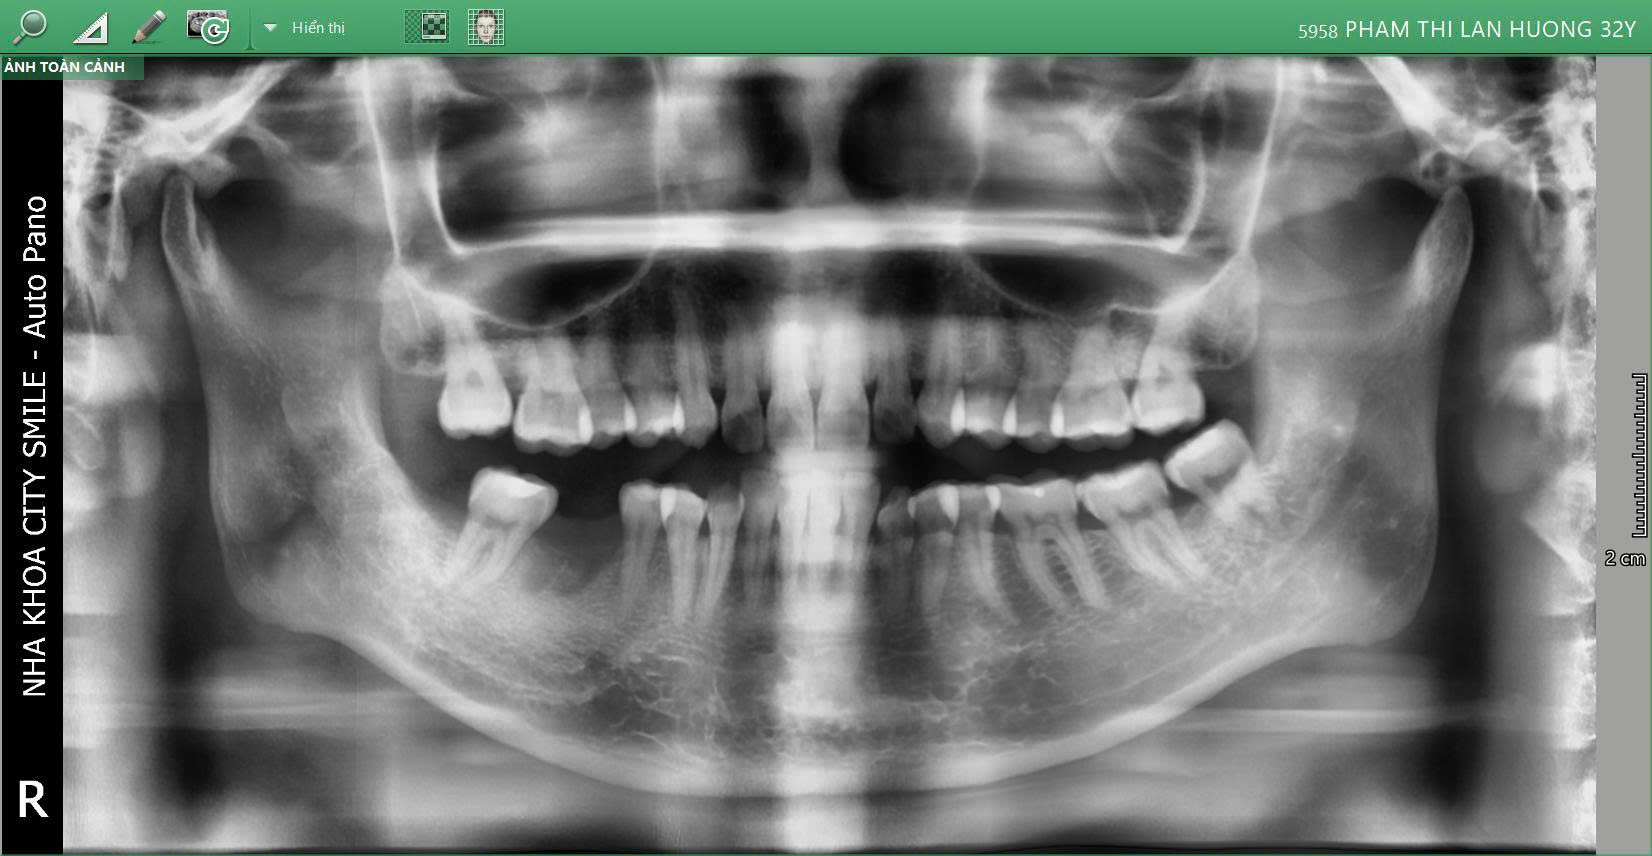

Chị Lan Hương – 30 tuổi đã lựa chọn City Smiles Tân Bình để phục hồi răng 46 bị mất bằng cắm trụ Implant ETK Pháp, giải pháp tối ưu giúp khôi phục chức năng ăn nhai và thẩm mỹ tự nhiên.

Tình trạng ban đầu

Răng 46 bị mất, ảnh hưởng chức năng ăn nhai

Nguy cơ tiêu xương vùng răng trống nếu không được phục hồi sớm